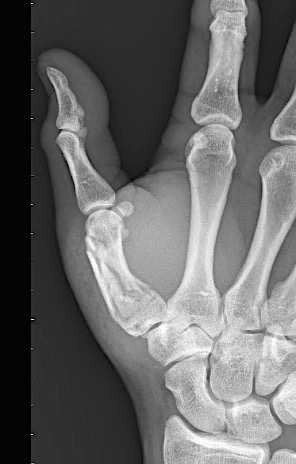

Case 1:

A 64-year-old male suffered a multi-fragmentary fracture of his right thumb metacarpal (Fig 1). An adapted 12-hole strut plate from the variable angle locking hand system was the implant of choice for fixation (Figs 2 - 4).

The strut plate provided good stability in a comminuted extraaricular fracture pattern and enables immediate mobilization. Bone callus formation was not witnessed during the healing process.